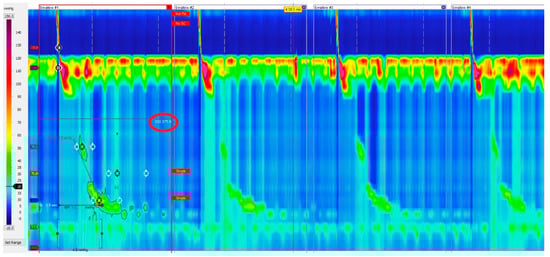

Esophagogastric Junction Outflow Obstruction